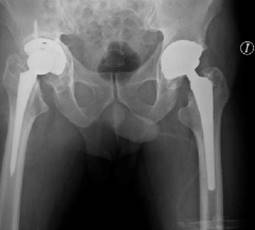

La artroplastía total de cadera se realizó con una prótesis con sistema DePuy Synthes de Johnson & Johnson (Warsaw, IN, USA) con una copa acetabular no cementada Pinnacle Porocoat Acetabular Shell Multi-Hole II de 58 mm, la cual se fija con tres tornillos de 6.5 × 20,2 y 30 mm,1 inserto de polietileno de 32 mm, cabeza femoral metálica de 32 mm +1 y vástago femoral no cementado Summit 12/14 estándar #1 de 125 mm. El reemplazo articular se llevó a cabo por medio de un abordaje lateral directo donde, previo a la colocación del componente acetabular, se impacta autoinjerto y aloinjerto de cabeza femoral con el apoyo de la rima acetabular en sentido reverso para posteriormente colocar malla de titanio (Figura 5). La herida se cubre con un apósito convencional estéril y se toma control radiológico postquirúrgico con una proyección anteroposterior de pelvis (Figura 6).

Figura 6: Radiografía anteroposterior de pelvis con resultado postquirúrgico de artroplastía total de cadera derecha posterior a impactación de injerto óseo y malla acetabular.

Durante el período postoperatorio, el paciente permaneció cuatro días hospitalizado, restringiendo el apoyo con peso de la extremidad pélvica derecha en todo momento y realizando traslados al reposet para favorecer la movilización continua y la liberación de puntos de presión. El paciente fue dado de alta clínica y hemodinámicamente estable, sin necesidad de transfusión de hemoderivados.

Durante su seguimiento en el período postoperatorio (6-12 semanas), el paciente continúa sin apoyo hasta la semana 4, en el cual comienza con apoyo completo a tolerancia aún acompañado de andadera como auxiliar de la marcha. Se lleva a cabo control radiológico a las cuatro y a las ocho semanas observando adecuadamente todos los componentes protésicos sin datos de osteólisis o aflojamiento. Actualmente se encuentra realizando actividades de la vida diaria con ligera limitación debido a la claudicación ocasionada por la incisión en el glúteo medio; sin embargo, expresó una gran satisfacción con el resultado funcional del procedimiento.